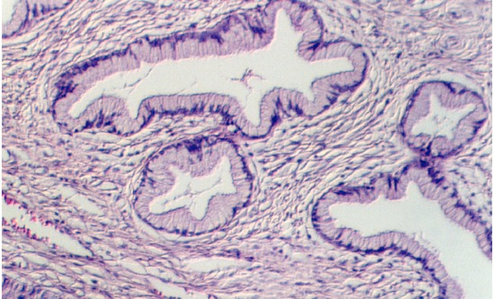

The uterus is a muscular sac, lined with epithelium that undergoes cyclic changes. The wall is made up of thick smooth muscle, organized in interlacing bundles that run randomly. It is called the myometrium In the above photograph, the uterine glands (a part of the endometrium) are seen as straight tubular glands leading to a main lumen. This is diagnostic of the early stage of the cycle or the Proliferative phase. What hormone is secreted by the follicle during this early stage of the cycle?

As stated above, the uterine lining consists of glands that are called "endometrium" As the ovary and oviduct are undergoing changes with the cycle, the uterine lining is being prepared to receive an embryo. The normal human menstral cycle is divided into three phases by the hormonal events and changes in the uterine lining. The first phase is called the Proliferative phase. This coincides with the rise in estrogens early in the cycle and is distinguished in the uterus by lengthening endometrial glands.

Slide 86 shows a uterus in the proliferative phase. The endometrium is illustrated in the photograph below. Note that the cells are low columnar to high columnar. The glands are relatively straight with a narrow lumina. Outside the glands is the highly cellular lamina propria. The following photos illustrate the proliferative phase with higher magnifications.